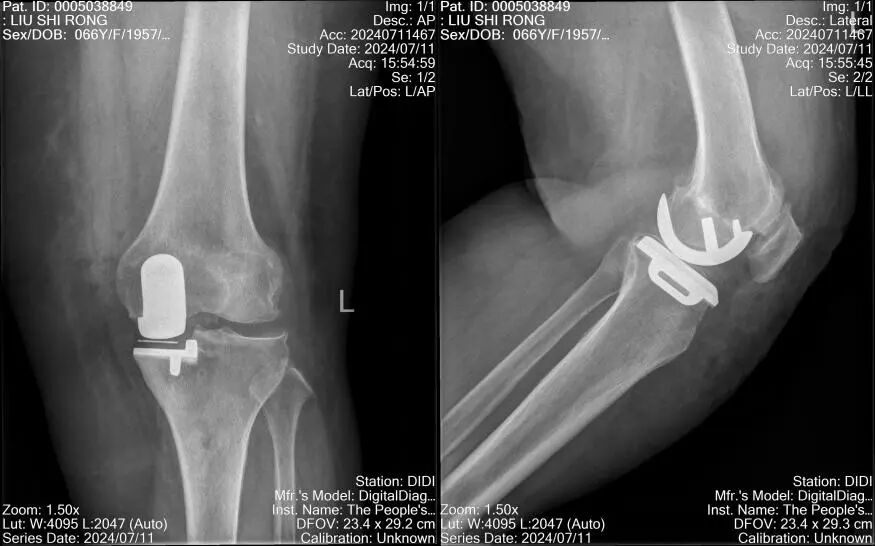

在麻醉科及手术室的积极配合下,手术仅用1小时就顺利结束,术后当天,郑奶奶就在助行器的辅助下下床行走活动,术后伤口愈合良好,疼痛明显减轻。

术后第5天,恢复良好的郑奶奶即要求出院,而且表示休养一段时间后,会再来进行住院手术治疗右膝关节的病痛,郑奶奶也充分意识到肥胖的危害,在饮食结构和习惯上发生了变化,体重正在逐渐下降。